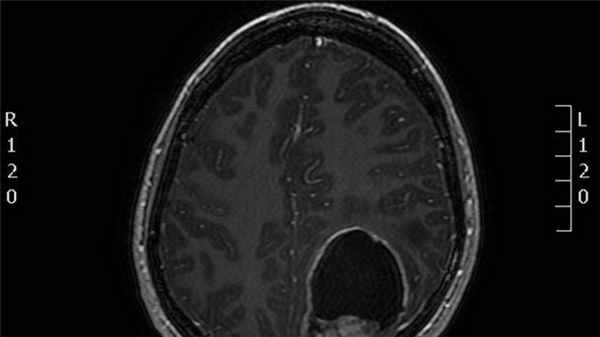

Супратенториальная эпендимома на МРТ

Эпендимома обычно представлена гетерогенным образованием с зонами некроза, кальцинатами, кистозной трансформацией и зачастую кровоизлияниями.

Интрапаренхиматозные поражения (как правило супратенториальные) обычно имеют более крупные размеры и вариабельность в проявлениях [7].- грубые кальцификаты (50%)

- кистозные зоны (50%)

- солидный компонент изо- и гиподенсивной плотности

- гетерогенное контрастное усиление

- кровоизлияния вариабельные

- T1

- солидный компонент эпендимомы обычно имеет изо- или гипоинтенсивный сигнал по отношению к белому веществу [7]

- гиперинтенсивный сигнал по отношению к белому веществу

- является более надежной последовательностью в дифференциально диагностике опухолевого поражения, чем бесконтрастные Т1 ВИ (но менее надежные чем Т1 с парамагнетиками)

- фокусы цветения за счет кровоизлияния или кальцификатов

- гетерогенное усиление

- полезно в разграничении опухоли от вазогенного отека и неизмененной паренхимы

- ограничение диффузии в солидном компоненте, особенно при анапластичпеском варианте

- интерпретация требует осторожности, поскольку может изменяться за счет кровоизлияний или кальцинатов